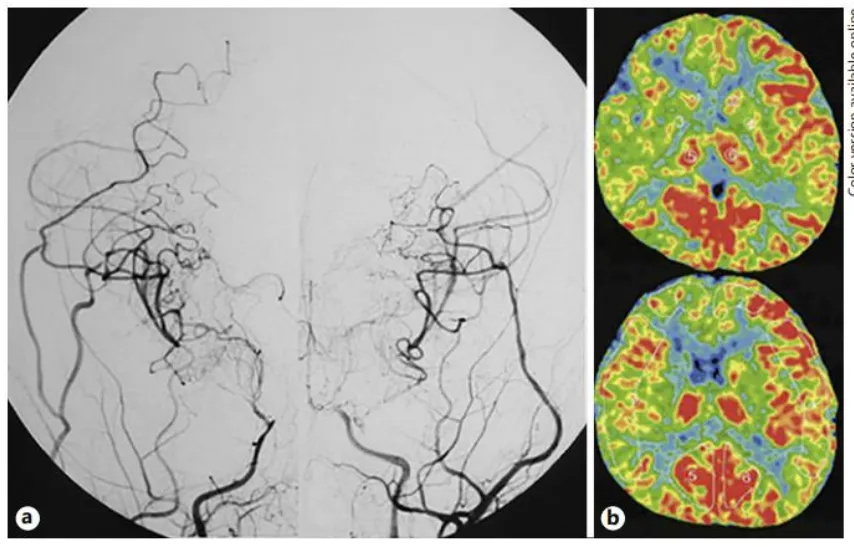

2岁的日本女孩桃子,正是无忧无虑快乐长大的年纪,然而父母好几次发现了孩子突然晕倒抽搐的症状,后期桃子的症状也越演越烈,发展为惊厥发作。父母赶紧送医检查,经过核磁共振血管造影(MRA),桃子父母被告知孩子可能得了“烟雾病”(MMD),脑DSA显示双侧ICA末端、大脑前动脉近端和MCA严重狭窄(图1)。相关检查显示右侧额叶CBF明显降低,并曾发生脑梗死。原来孩子早先的卒阙早有苗头,都是因为这个“烟雾病”作祟。桃子需要住院做进一步检查和治疗。

图1.a双侧CTA显示左侧颈内动脉血管严重狭窄,颈内动脉的末端前部和中部的动脉和起源可见于两侧的脑动脉,还可以看到“烟雾动脉。

右侧额叶明显的脑血流减少、代谢低,提示既往脑梗病史。